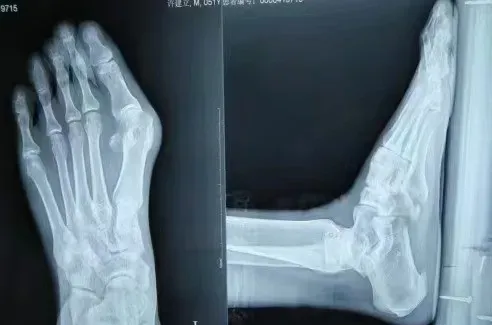

上图为术前术后对比图

术前术后X光片对比图